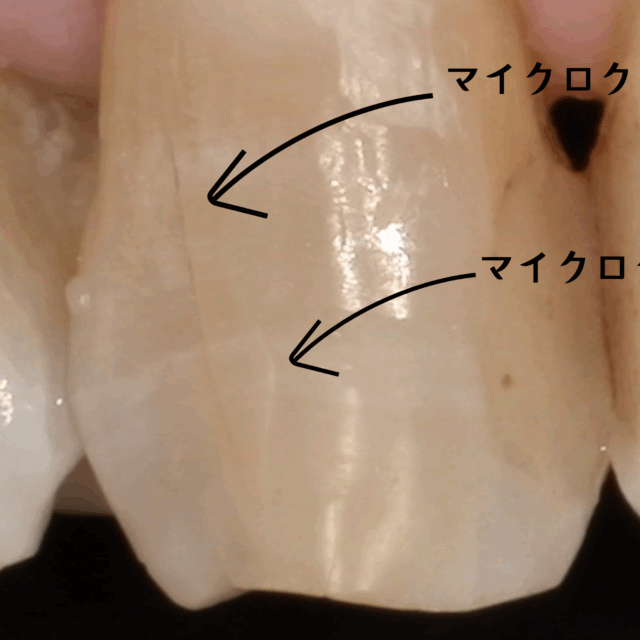

あなたの歯にもあるかも…歯のヒビの話